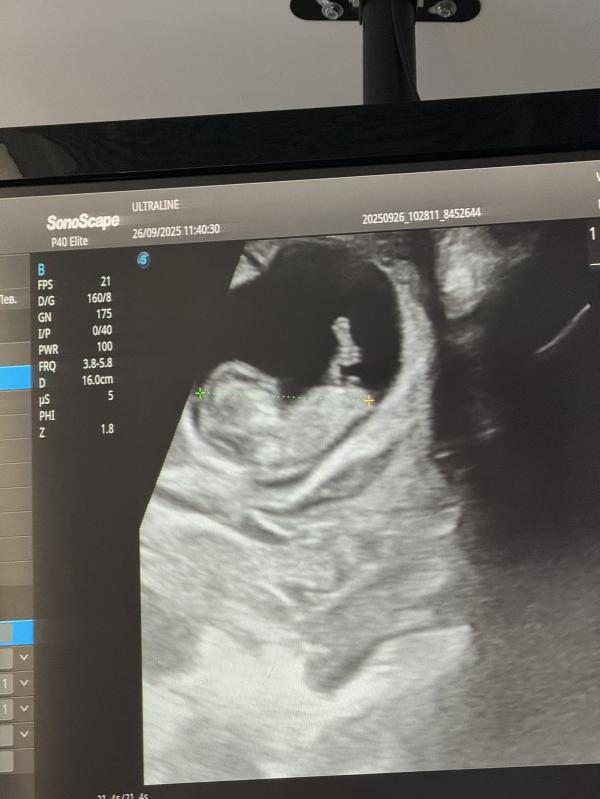

Девочки, кто нибудь узнавал пол на 13 неделе? Совпало у вас? Есть в Астане хороший УЗИ специалист, который определяет на этом сроке?

Читала на маленьких сроках если смотрит прям вверх это мальчик , если косо по диагонали то девочка.